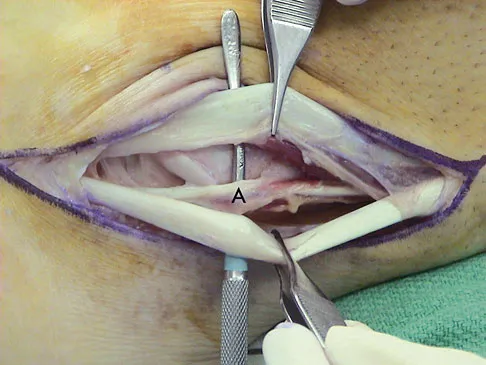

Question 62

A 35-year-old man is seen for evaluation of his left ankle following multiple previous ankle sprains and frequent episodes of the ankle giving way. Examination reveals marked laxity about the lateral ankle with associated tenderness along the peroneal tendons. Physical therapy, anti-inflammatory drugs, and supportive bracing have failed to provide relief. An MRI scan shows peroneal tenosynovitis and a possible tear. He elects to undergo a peroneal tendon repair and lateral ligament reconstruction. Which of the following best describes the structure labeled "A" in Figure 45?

Explanation